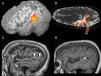

La afasia es una alteración adquirida del lenguaje debida a una lesión cerebral, que se caracteriza por errores en la producción, la denominación o la comprensión del lenguaje. Aunque la mayoría de las afasias suelen ser mixtas, desde un punto de vista práctico se clasifican en diferentes tipos según sus rasgos clínicos principales: afasia de Broca, afasia de Wernicke, afasia de conducción, afasia transcortical y alexia con o sin agrafia. Presentamos los hallazgos clínicos de los principales subtipos representándolos con casos radiológicos, y proporcionamos una revisión actualizada de la red del lenguaje con imágenes de resonancia funcional y de tractografía.

Aphasia is an acquired language disorder due to a cerebral lesion; it is characterized by errors in production, denomination, or comprehension of language. Although most aphasias are mixed, from a practical point of view they are classified into different types according to their main clinical features: Broca's aphasia, Wernicke's aphasia, conduction aphasia, transcortical aphasia, and alexia with or without agraphia. We present the clinical findings for the main subtypes of aphasia, illustrating them with imaging cases, and we provide an up-to-date review of the language network with images from functional magnetic resonance imaging and tractography.